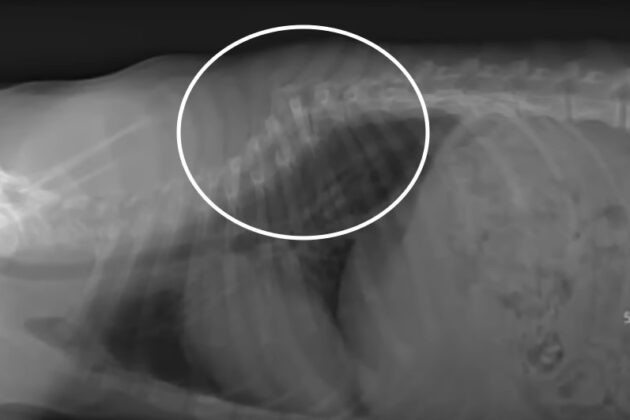

His ordeal was evident from his red eyes, but the true extent of his suffering was revealed when it became clear that his spinal cord was damaged. Sadly, if help had come sooner, his chances for recovery might have been better.

With immense determination, he eventually managed to sit up. This was a monumental achievement for him, and with the assistance of a wheelchair, he began to experience a more normal life, all thanks to the tireless efforts of his rescuers.